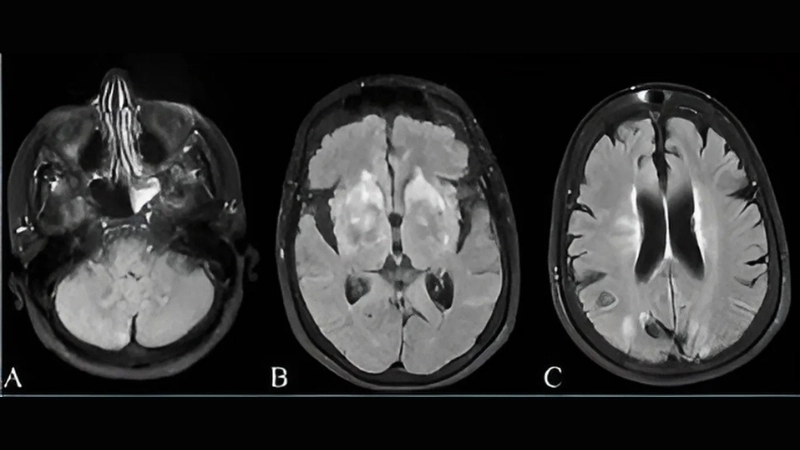

Image description of Powassan Encephalitis

Powassan Encephalitis is a rare, tick-borne viral infection that affects the brain. It can cause fever, headache, and severe neurological complications if left untreated.